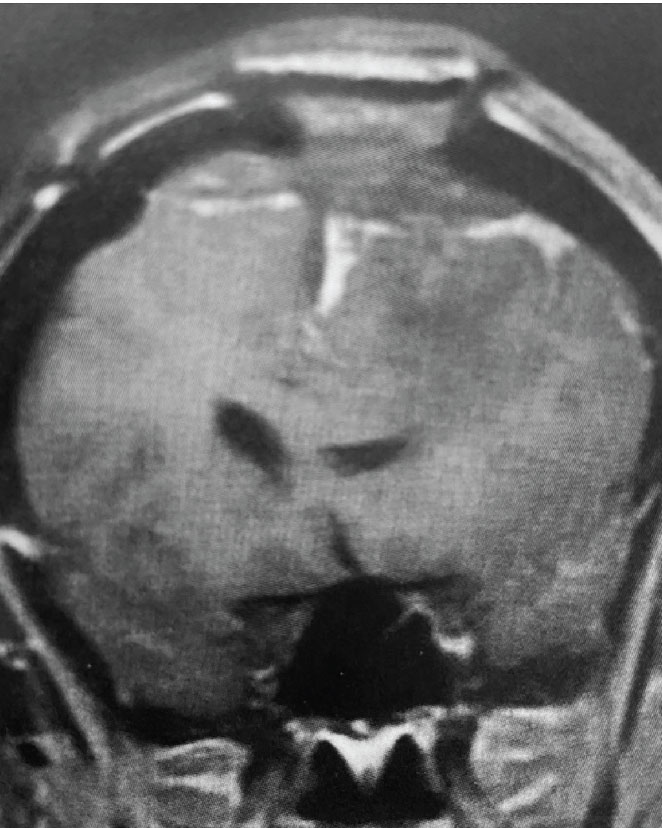

Fig 1. A) Pre-operative, post-contrast, coronal MRI. Arrow points to tumor involvement in the superior sagittal sinus.

Meningiomas that involve the superior sagittal sinus: Sometimes convexity or falx meningiomas will grow into the superior sagittal sinus. Sometimes the sinus can become completely occluded. Usually this occurs over many years, and as such, the brain has time to develop venous collaterals. So, while in a normal person, sudden occlusion of the superior sagittal sinus could lead to venous infarction or death, the very gradual occlusion that can be seen with meningiomas, does not lead to these problems. Also, if the sinus is filled with tumor and completely occluded, it can usually be safely removed at that segment.

This is a 55 year old right-handed woman who was having progressive balance problems. MRI with and without contrast demonstrated a 7 cm partly cystic meningioma involving the left frontal convexity and falx, and encasing the superior sagittal sinus. There was also tumor involvement of part of the convexity skull.